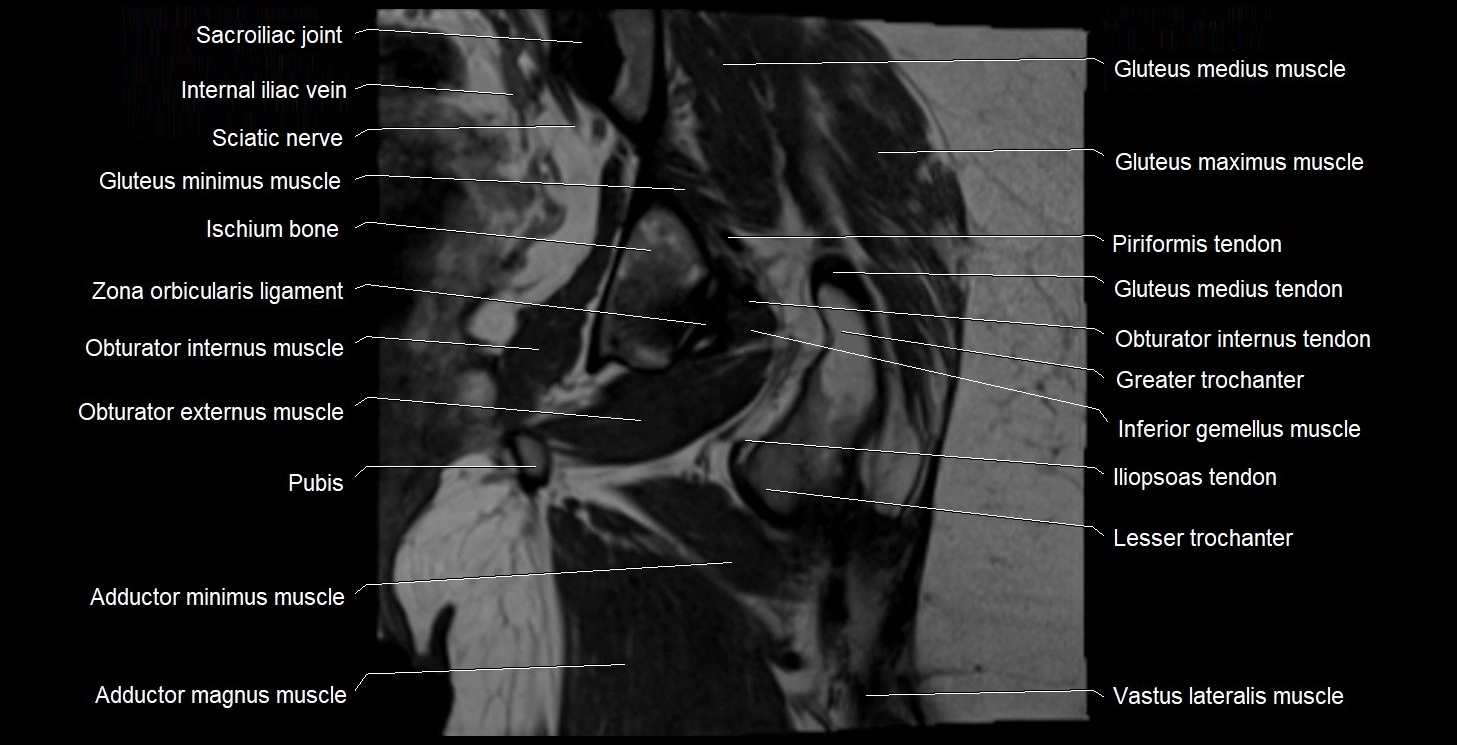

- Gluteus maximus muscle

- Gluteus medius muscle

- Gluteus medius tendon

- Greater trochanter

- Head of femur

- Iliopsoas tendon

- Inferior gemellus muscle

- Ischiofemoral ligament

- Ischium bone

- Lesser trochanter

- Lumbosacral trunk

- Obturator externus muscle

- Obturator internus muscle

- Obturator internus tendon

- Quadratus femoris muscle

- Sacroiliac joint

- Superior gemellus muscle

- Vastus intermedius muscle

- Vastus lateralis muscle

- Zona orbicularis ligament